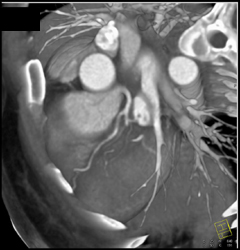

Beautiful Patent RCA Stent